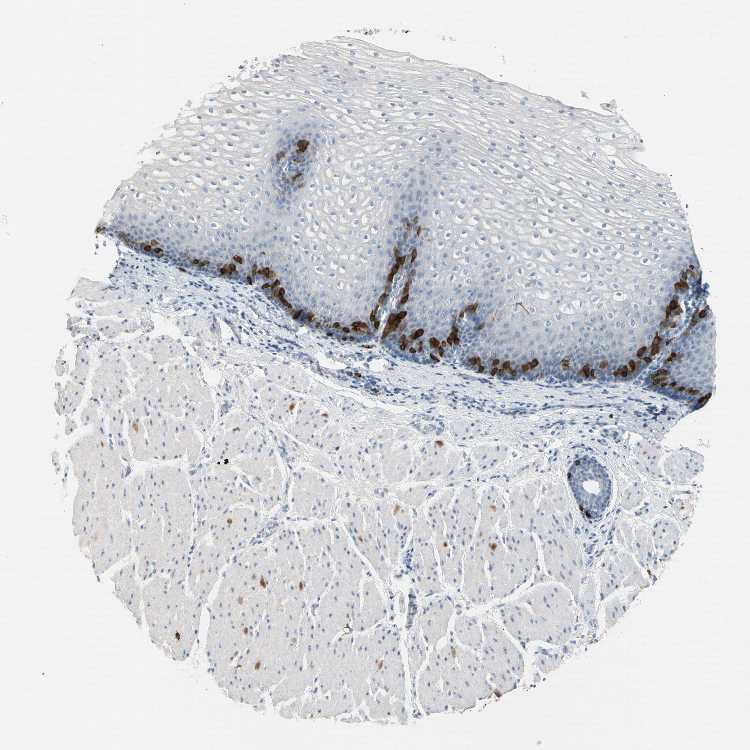

ESOPHAGUS - Antibody stainingi

Antibody staining in the annotated cell types in the current human tissue is reported as not detected, low, medium, or high, based on conventional immunohistochemistry profiling in selected tissues. This score is based on the combination of the staining intensity and fraction of stained cells.

Each image is clickable and will lead to virtual microscopy that enables deeper exploration of all samples and also displays staining intensity scores, fraction scores and subcellular localization as well as patient and tissue information for each sample.

Antibody HPA005781Antibody HPA022039Antibody CAB010111

Squamous epithelial cells LowNot detectedMedium